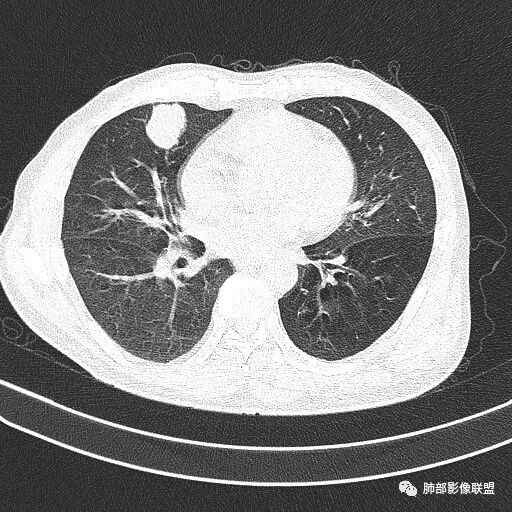

浅分叶

边缘膨隆

常规会考虑恶性

细胞类型我觉得还是让病理去定吧

薇:各位老师,下面是该病例的横断位薄层

1.右肺中叶孤立不规则块影,浅分叶,未见液化或钙化,未见毛刺,未见脐凹,未见明显胸膜牵拉。

2.近肺门侧隐约见支气管截止。

3.外侧可见血管进入,病灶局部轻度强化。